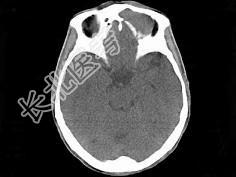

- 单项选择题男,53岁, 近两年来渐进性头痛,伴左眼球外突, 并向前下方移位,CT检查如图, 最可能诊断为 ( )